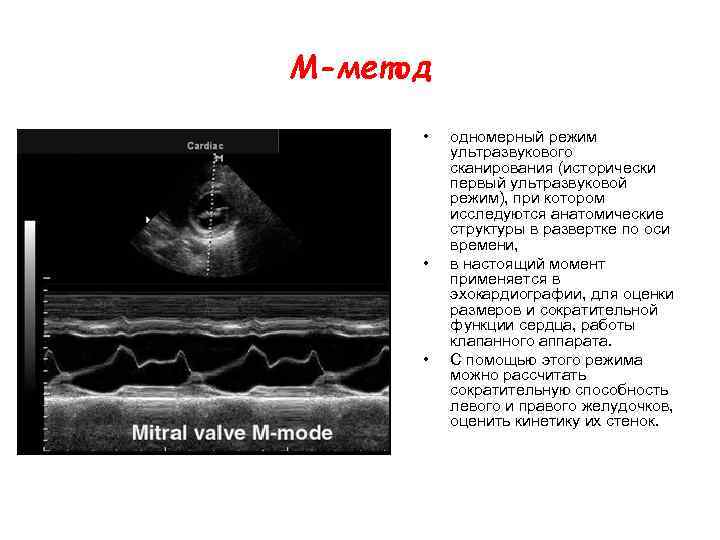

М-метод • • • одномерный режим ультразвукового сканирования (исторически первый ультразвуковой режим), при котором исследуются анатомические структуры в развертке по оси времени, в настоящий момент применяется в эхокардиографии, для оценки размеров и сократительной функции сердца, работы клапанного аппарата. С помощью этого режима можно рассчитать сократительную способность левого и правого желудочков, оценить кинетику их стенок.

М-метод • • • одномерный режим ультразвукового сканирования (исторически первый ультразвуковой режим), при котором исследуются анатомические структуры в развертке по оси времени, в настоящий момент применяется в эхокардиографии, для оценки размеров и сократительной функции сердца, работы клапанного аппарата. С помощью этого режима можно рассчитать сократительную способность левого и правого желудочков, оценить кинетику их стенок.

M-mode (M-режим) - оценка сократительной функции желудочков • При исследовании в М-режиме принципиально важным является выбор правильной позиции сканирования, например, для исключения отображения движения папиллярных мышц M-курсор должен быть установлен в парастернальной позиции по короткой оси (right parasternal axis view).

M-mode (M-режим) - оценка сократительной функции желудочков • При исследовании в М-режиме принципиально важным является выбор правильной позиции сканирования, например, для исключения отображения движения папиллярных мышц M-курсор должен быть установлен в парастернальной позиции по короткой оси (right parasternal axis view).